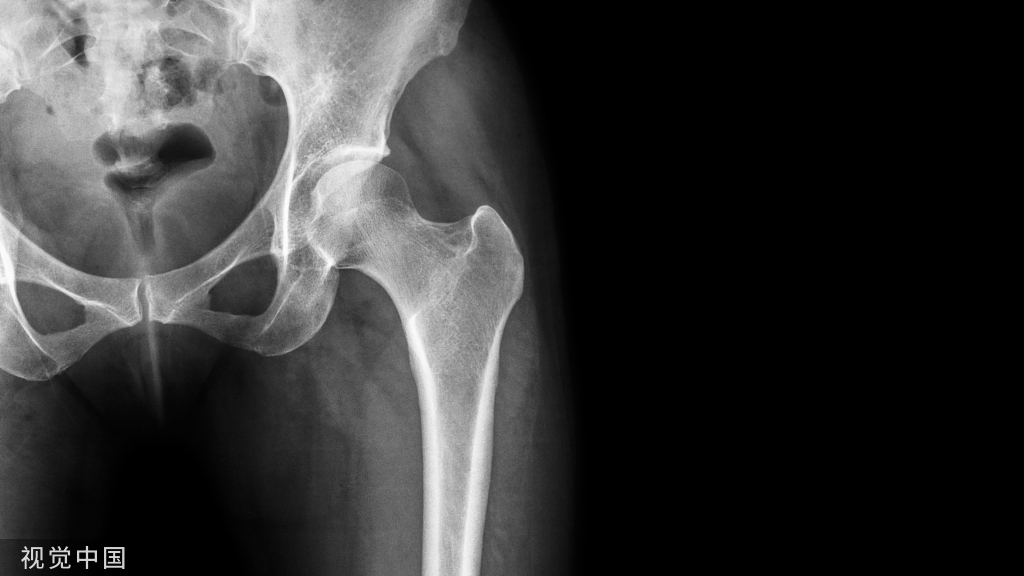

3、大结节骨折

4、大粗隆骨折